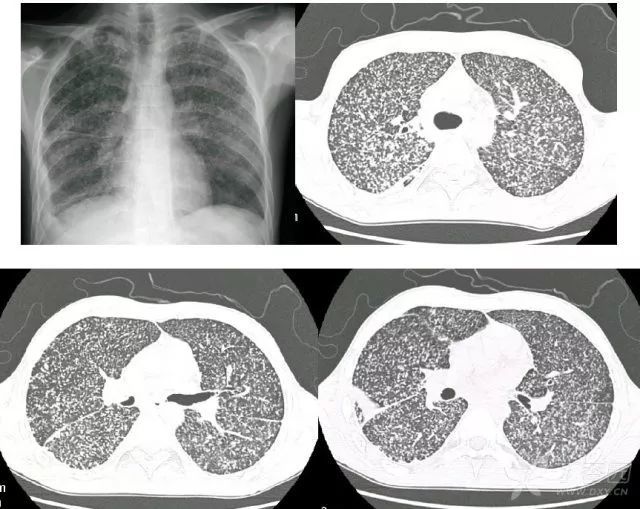

肺肿瘤ct影像图片,肺部肿瘤图片ct光片

肺部肿瘤图片ct光片

肺癌ct影像图片

肺肿瘤ct图片表现

肺部肿瘤ct图片显示图

肺部肿瘤ct图片